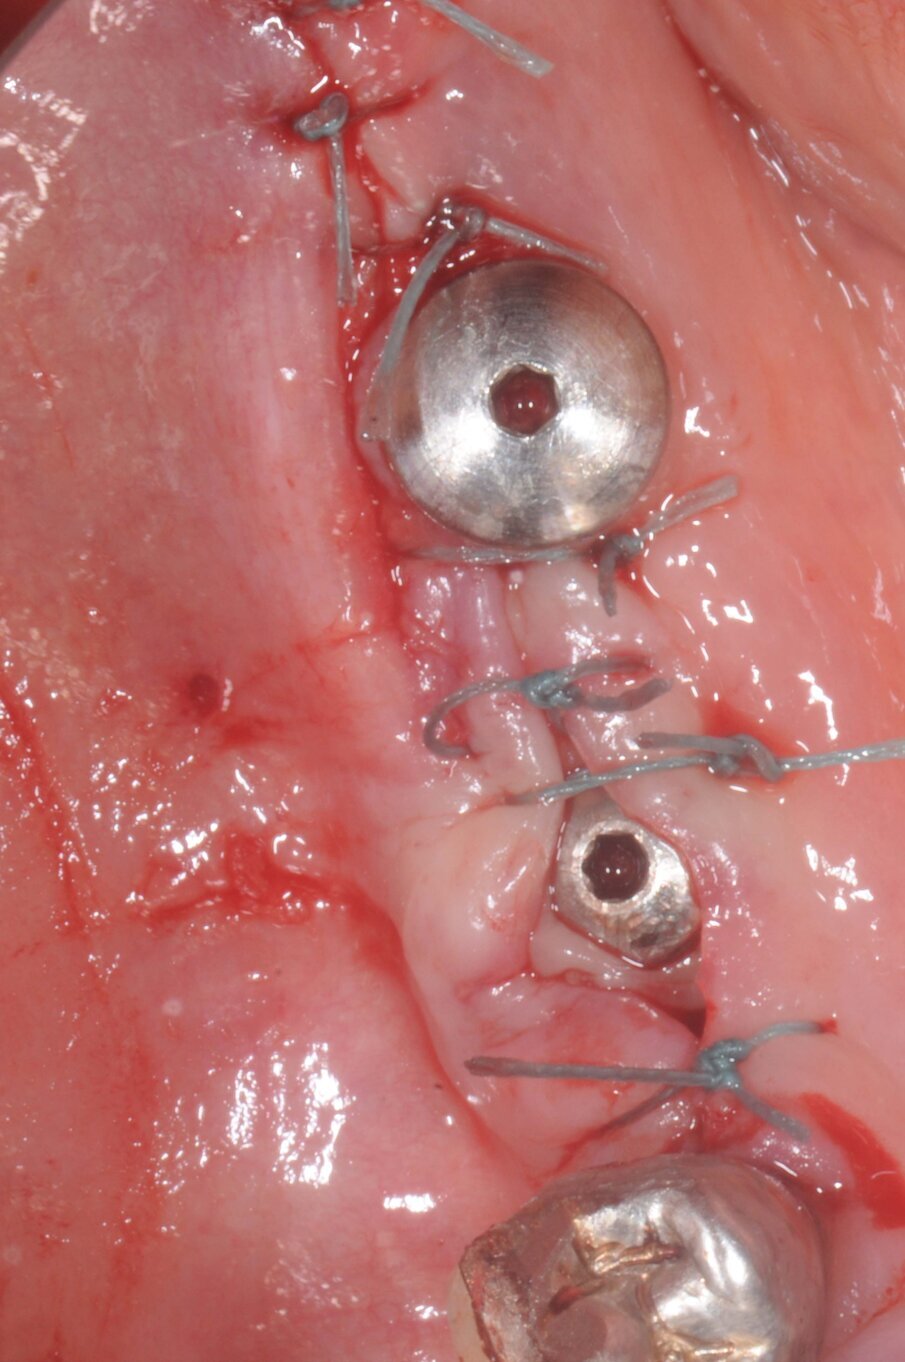

La terapia anticoagulante non è stata interrotta prima della chirurgia ed è stata somministrata la profilassi antibiotica come da protocollo. È stata eseguita un’incisione crestale senza tagli di scarico che è stata estese distalmente fino al trigono retromolare per esporre la branca mandibolare ed avere un sito per raccogliere osso autologo con una fresa carotatrice. Sono state eseguite le osteotomie a basso numero di giri come da protocollo BTI per ottenere un’ulteriore quantità di osso autologo raccolto dalle frese e inseriti due impianti BTI Core 3,75 x 4,5 e 3,5 x 6,5 rispettivamente in posizione 46 e 45.

L’osso autologo è stato mescolato con gel piastrino ottenuto da centrifugazione del sangue del paziente mediante metodica Endoret BTI. La membrana ottenuta è stata applicata a protezione della corticale vestibolare. Ulteriori membrane di gel piastrino sono state applicate sopra l’osso autologo. La stabilita primaria di entrambi gli impianti era superiore ai 50 Newton per cui sono stati avvitati i pilastri Multi-Im e i pilastri di guarigione per un tecnica con una sola chirurgia. Sono state applicate suture sintetiche non riassorbibili a punti staccati (Figg. 3–10). Successivamente è stata eseguita una Rx di controllo. Le suture sono state rimosse a due settimane e la paziente riferì di avere avuto disagi minimi, senza ematomi o edemi estesi e scarsa dolenzia che non richiese l’assunzione di antinfiammatori.